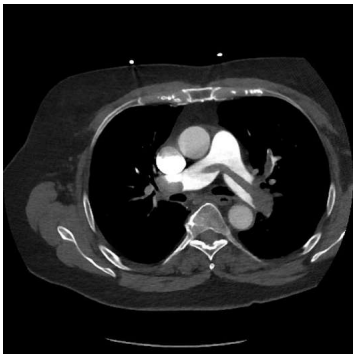

Um homem de 62 anos de idade, com câncer de pâncreas

metastático, apresentou-se com dispneia, dor torácica

ventilatório dependente e palpitações. Na admissão,

detectou-se que o paciente era hipotenso, taquicardíaco e

que estava com queda de saturação. Exames apontaram: PA

83x62 mmHg; FC de 128 bpm; ECG em ritmo de fibrilação

atrial; pocus com sinal de McConnell; e veia cava túrgida. A

angio TC de tórax está disposta na imagem a seguir.